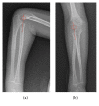

An Undescribed Monteggia Type 3 Equivalent Lesion: Lateral Dislocation of Radial Head with Both-Bone Forearm Fracture

Monteggia fractures are accepted as hard-to-recognize and easy-to-handle fractures. Adequate radiographic investigations and clinical examinations are necessities. This case holds unique features involving diagnosis and treatment. In this case, the radial head was dislocated laterally while both bones were fractured in the proximal diaphysis, being the first to be mentioned in the literature. Closed reduction of the ulna is the preferred method of handling and almost always results in reduction of the radial head. Literature obligates ulnar reduction as a preliminary to reduce and stabilize the radial head. Closed reduction reduced the ulna but the radial head was not reduced. Hence an intramedullary K-wire was used to reduce the radial head and a long arm cast was used to stabilize the reduction. The operation was successful and follow-up showed no complications.